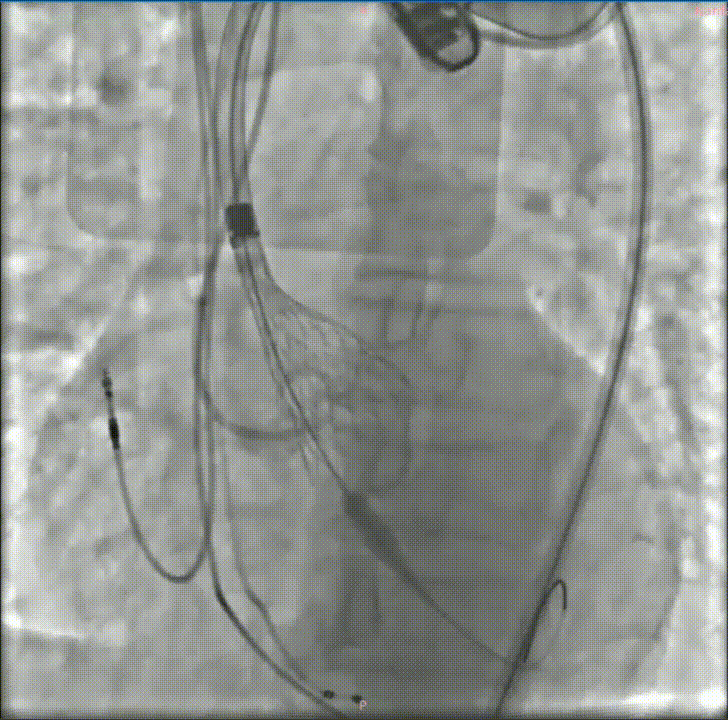

经过充分的术前评估和准备,修建成教授带领由医院心内、超声、麻醉、放射等多学科成员组成的手术团队,开始了这台TAVR手术。

穿刺、置管、跨瓣、扩张、释放瓣膜、测压、检测、拔管、手术结束……当天的DSA手术台上,修建成教授和团队有条不紊地完成着每一个步骤。术中的每一个步骤、每一个节点、每一个动作,团队每位成员都十分娴熟。最终成功在预定位置精准植入瓣膜。

深度评估

释放后造影

后扩

瓣膜植入后立即进入工作状态,术后造影显示瓣膜工作状态良好,无瓣周漏及明显跨瓣压差;冠脉无阻挡,无传导阻滞

采访中,修建成教授欣慰地分享了手术效果:“手术之后的结果也验证了我们术前的分析和想法。从影像学结果分析来看,我们把瓣周漏减少到非常低的水平,同时瓣膜的扩张、展开都非常好,可以说达到一个非常理想的结果。”